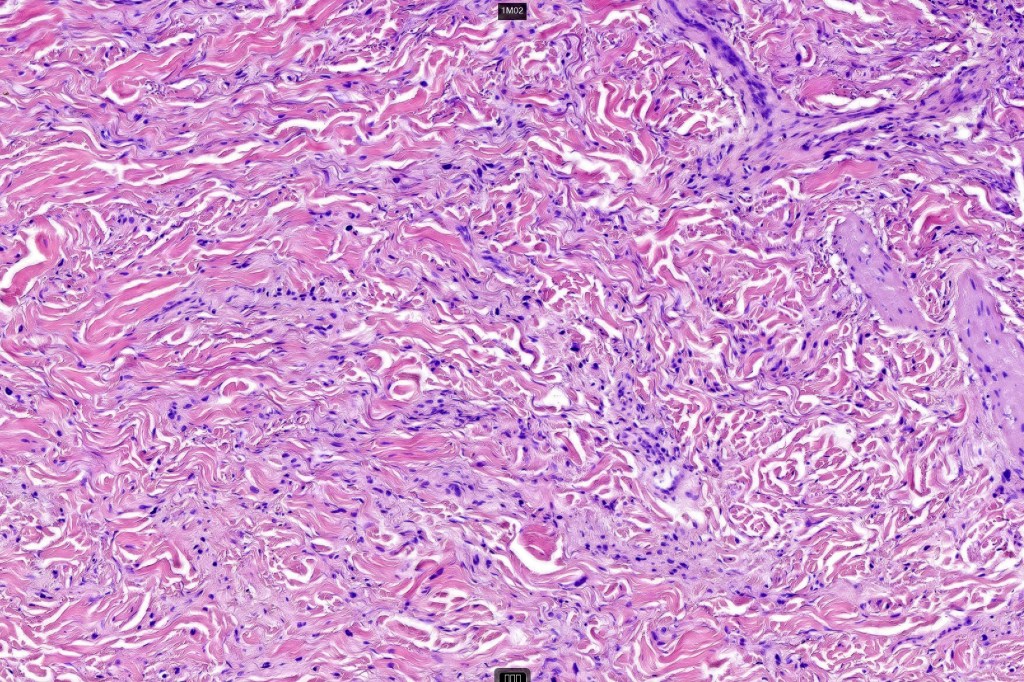

•Paucicellular spindle cell infiltrate with “myxoid” fine to a dense collagenous stroma

•Neurotropism

•Neural transformation